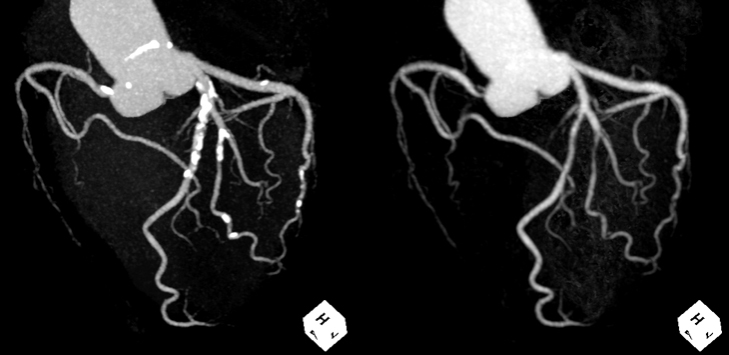

これまで、CTでは評価が難しいとされている冠動脈の強い石灰化部位やステント治療部位において、我々が考案した特殊な撮影(test bolus tracking法)および画像処理技術を用いて評価可能な画像を可能な限り提供しています。

通常の画像(左)に比べ、石灰化(白い部分)を除去した画像(右)では血管狭窄の有無が明瞭に評価できます。

通常の画像(左)ではSTENT内の評価は困難ですが、サブトラクション画像(中央)によって末梢側に高度狭窄を疑われます(矢印)。カテーテル造影(右)でも同様の位置に高度狭窄病変を認めます(矢印)。

Yamaguchi T. Ichikawa K, Takahashi D. et.al. A New Contrast Enhancement Protocol for Subtraction Coronary Computed Tomography Requiring a Short Breath-Holding Time. Academic Radiology Published online: October 17, 2016